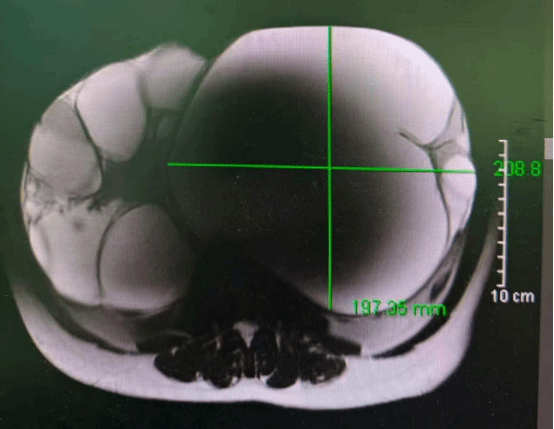

十年抗瘤路终迎破茧——多学科护航患者重获健康

25cm巨大肿瘤盘踞盆腔,十年间历经3次手术与化疗,恐惧让她一度犹豫就医......近日,第五附属医院妇科刘芳主任团队,联合普通外科、麻醉科等多学科力量,成功为一名复发性卵巢交界性肿瘤患者实施高难度手术,完整切除肿瘤并完成全面分期手术,助其摆脱十余年病痛阴霾,重获健康新生。十年抗争,肿瘤再度来袭患者与卵巢交界性肿瘤的搏斗已长达十余年。期间,她经历了3次手术和化疗,承受…